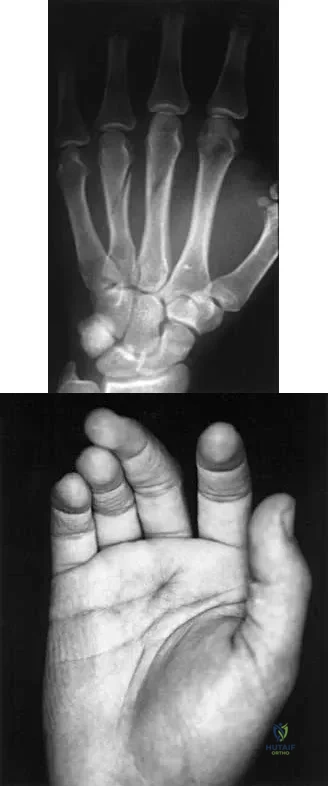

Question 66

A 23-year-old woman sustains an injury to her right hand after falling off her snowboard. Examination reveals that she has difficulty moving her fingers. A radiograph and a clinical photograph are shown in Figures 8a and Figure 8b. Management should consist of

Explanation